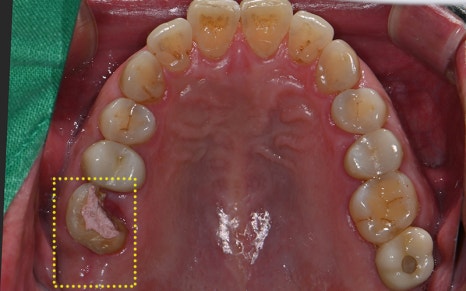

We also took an intraoral camera image

to carefully check the condition inside the mouth,

and explained it to the patient while showing it to them.

✅ Problems seen on X-ray